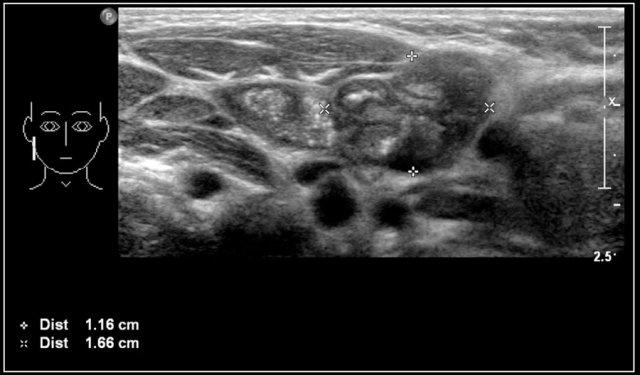

Hình ảnh của một bé trai mười bốn tuổi với khối sưng không đau ở cổ bên trái.

Siêu âm cho thấy nhiều hạch bạch huyết giảm âm phóng to, không có rốn hạch tăng âm.